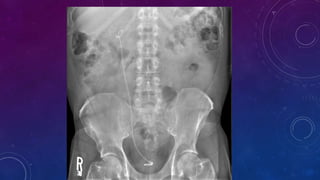

• Multiple pelvic phleboliths.

• Small well-defined round osseous lesions in the left

side of the abdomen, adjacent to midline represent

calcified lymph node in the para-aortic and left

common iliac groups, also visualized on the

corresponding CT.